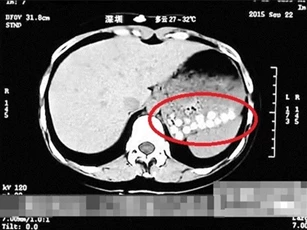

Người đàn ông 40 tuổi, sống ở Trung Quốc, nhập viện trong tình trạng mất cảm giác từ ngực trở xuống.